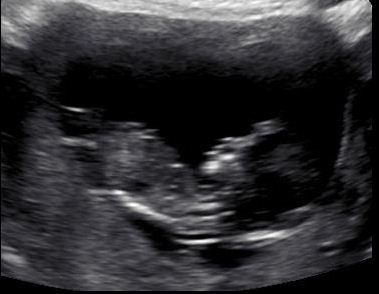

I hope you may be able to see a nub and be able to give me an idea of whether we have a pinkie or a bluey coming!! These pics were from about 12+5.

maybe boy skull